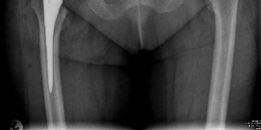

- This final image likely represents a post-operative radiograph of a successfully implanted uncemented acetabular component, demonstrating good position and fixation.